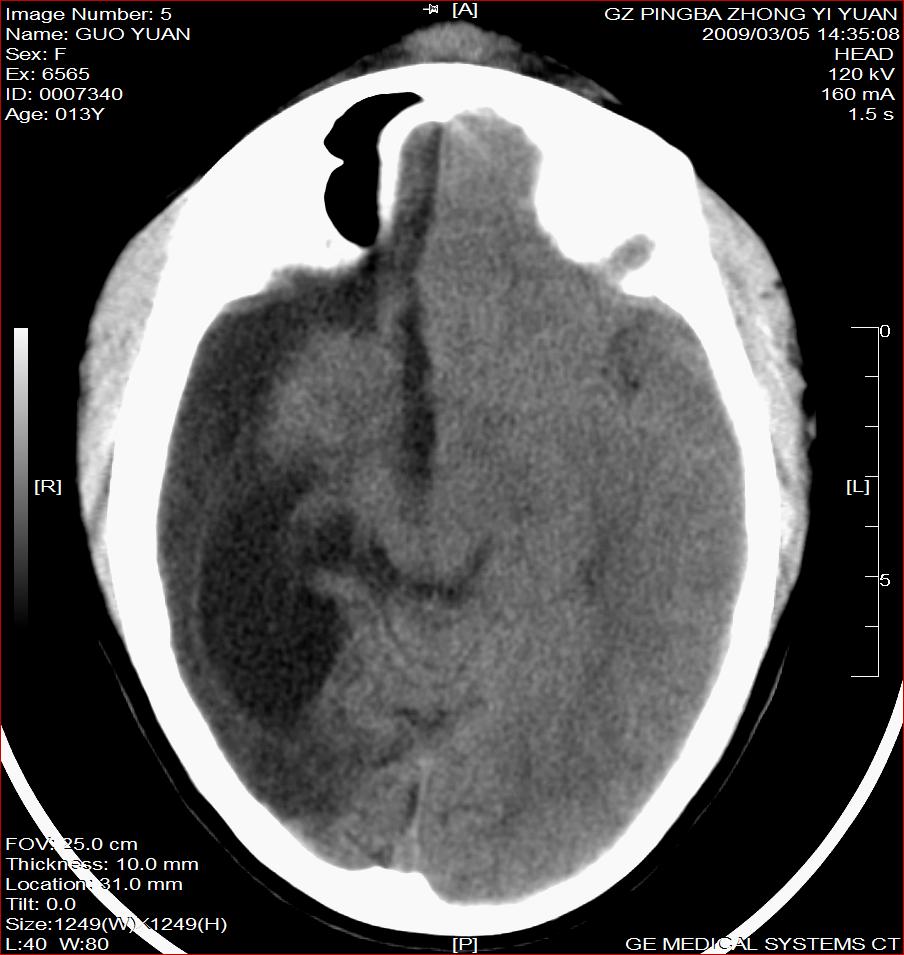

以下是引用杀毒软件在2009-3-6 17:32:00的发言:[br]右侧额颞顶部脑沟裂增宽,颞顶部楔形稍低密度影,侧脑室体部明显增宽,余脑实质内未见异常,中线结构居中。[br][br]考虑---右侧大脑半球发育不良并脑沟裂发育畸型可能性大

以下是引用随光逐影在2009-3-6 18:35:00的发言:[br]1)考虑右侧幕上半球发育不良并脑软化灶。2)双侧额部头皮软组织肿胀。